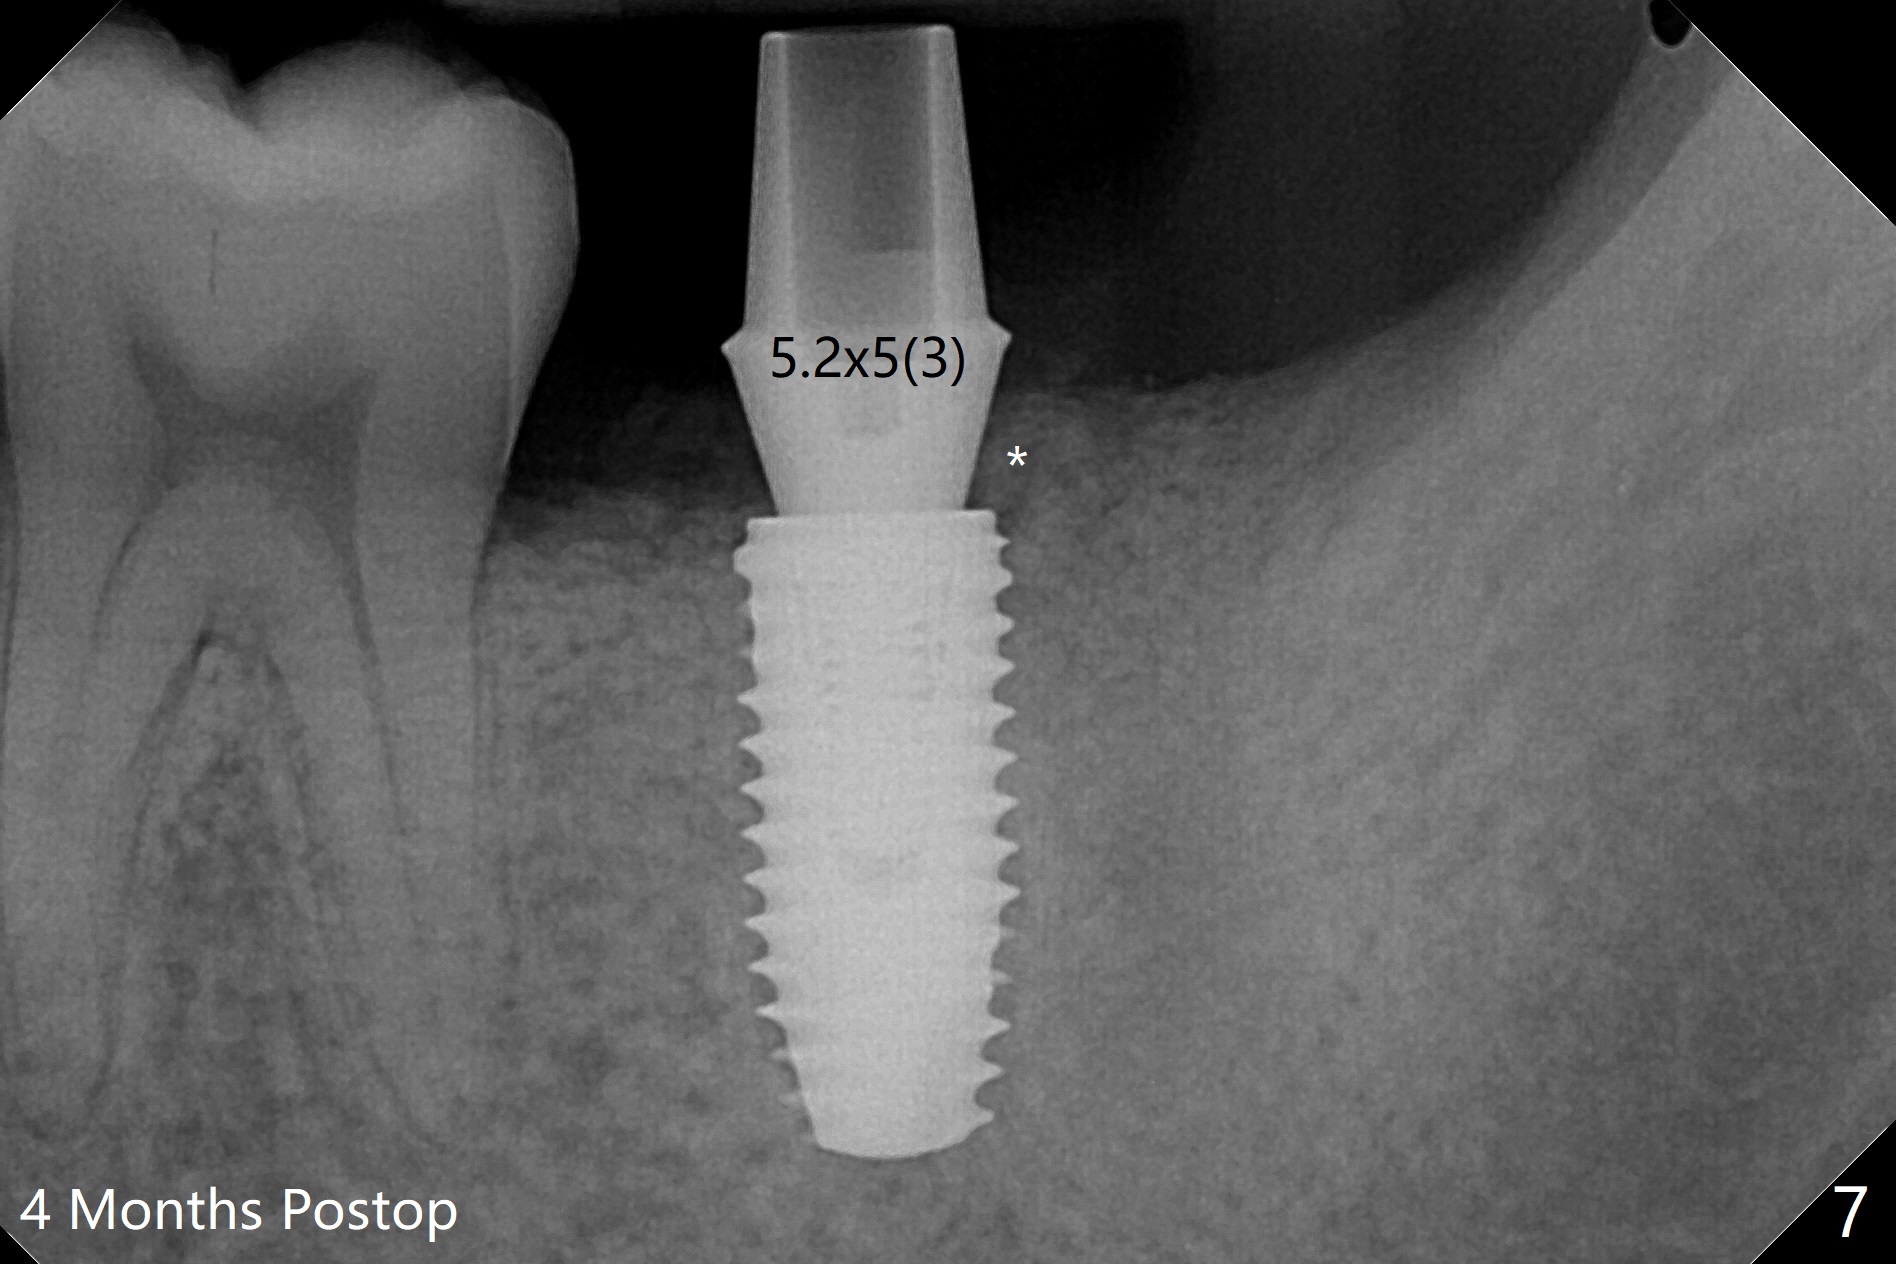

即刻种植即刻修复偶尔出现骨粉丧失,今天我们尝试临时基台,它可以制作像螺丝固位牙冠,可能会减少骨粉流失。左下7颊侧肿胀(图一:*),为了让植体(图二:绿色)植入中隔正中,钻洞时保留近中(M),远中(D)牙根。但是意想不到的是在导板指引下,钻头还是偏移近中(图三),而且颊侧(图四:圆圈),不过颊侧骨板没有缺损。由于牙根存在(硬),钻洞吃力,之后拔除,完成最后一个钻头,放置植体(图五),方位仿佛不错,临时基台(5.2x8(2)毫米)也完全就位,树脂围绕基台制作临时牙冠(图六),最后使用螺丝固位(*),颊侧肿胀牙龈必须用缝线固定(<),减少骨粉损失。由于牙冠与基台连接不好,病人汇报有些骨粉丢失。术后一个月检查尚可愈合正常,病人满意,已经做好思想准备做右下第二磨牙种植。临时牙冠进行修整。术后即刻近中牙槽窝间隙由粘性骨粉充填(图五),四个月后间隙消失(硬骨板也消失,图七),5.2x5(3)毫米粘固基台似乎没有完全就位,可能因为远中牙槽嵴阻挡(图七:*)。小一号基台仿佛完全就位(图八(咬翼片);图七(根尖片,可能失真)),但是临床上没有听到清脆声音(可能软硬组织阻挡)。随着时间推移,远中牙槽嵴吸收,当松动基台螺丝再次拧紧,可能会真正完全就位,必须拍摄完美咬翼片证实。这种植体芯(body, not threads)特别厚内部结构看不清楚。两周后粘固牙冠,然后取出牙冠和基台,清除残余粘固剂,然后复位,拧紧30Ncm。